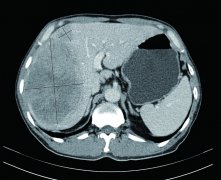

新法降服巨大肝癌 ——記普外科腫瘤的降期后手術(shù)切除治愈巨大